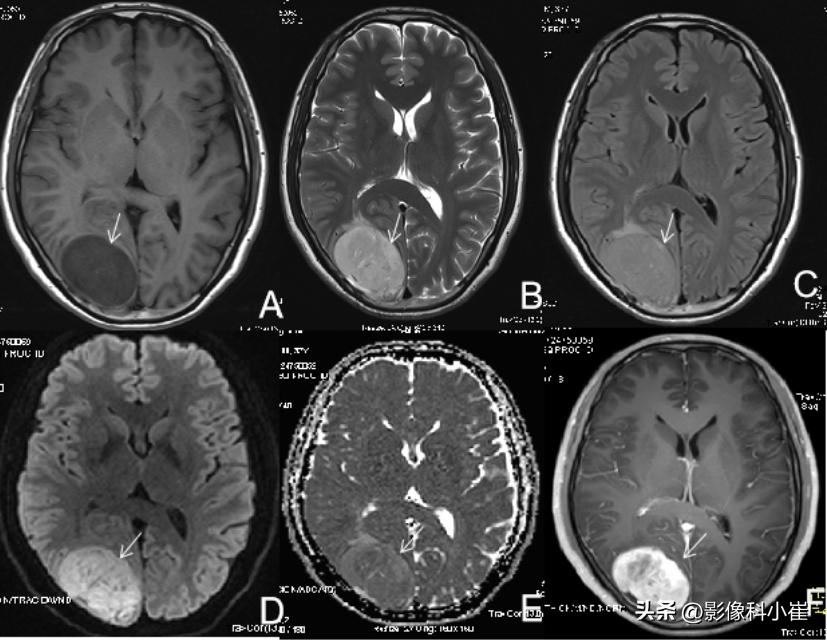

轴位T1WI(图A)示右侧枕叶类圆形等信号,边界清楚,T2WI(图B)呈略高信号,T2-FLAIR呈低信号,DWI(b=1000)呈略高信号,轴位强化(图F)示明显强化。

脑膜瘤。